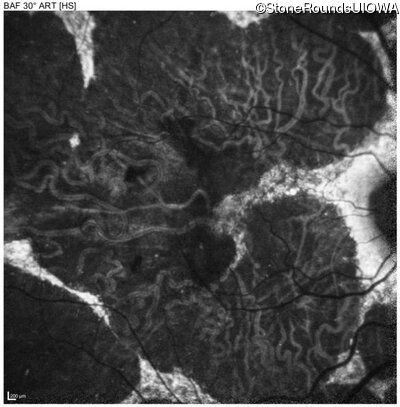

Blue Autofluorescence - Right - 20/40 -2

Exemplar